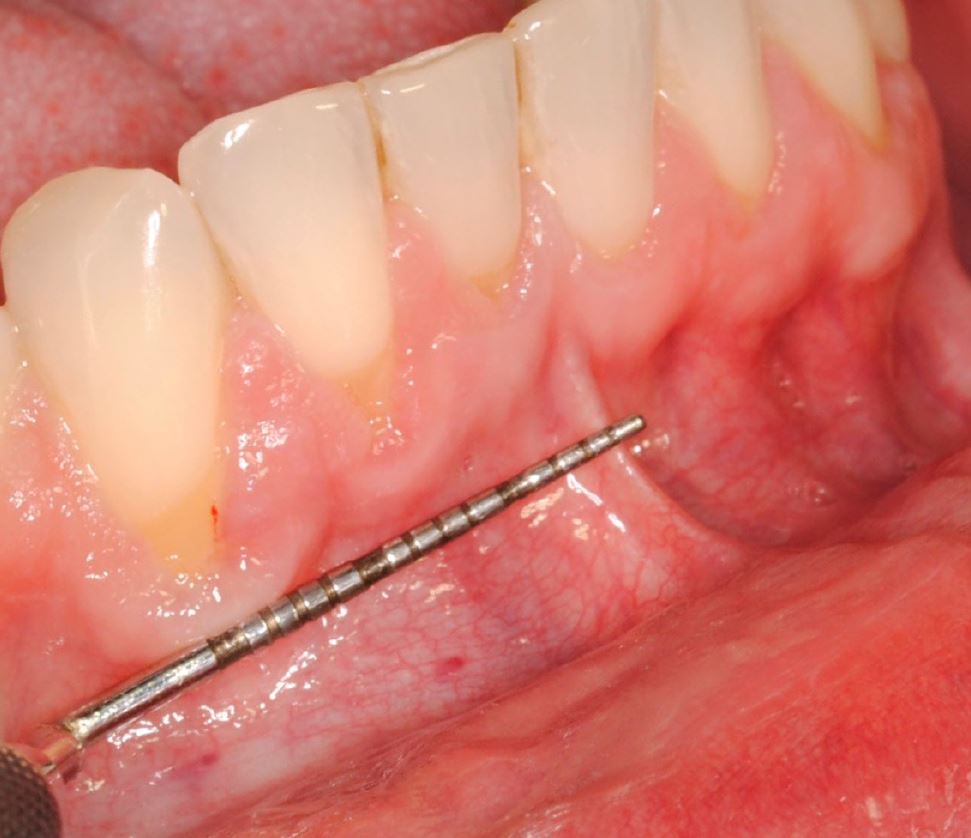

Objetivos periodontales: Mediante ingerto de tejido conectivo subepitelial de paladar con técnica de tunelización.

- Injerto de tejido conectivo libre desepitelizado de paladar + Tunelización

Fotografías del proceso: